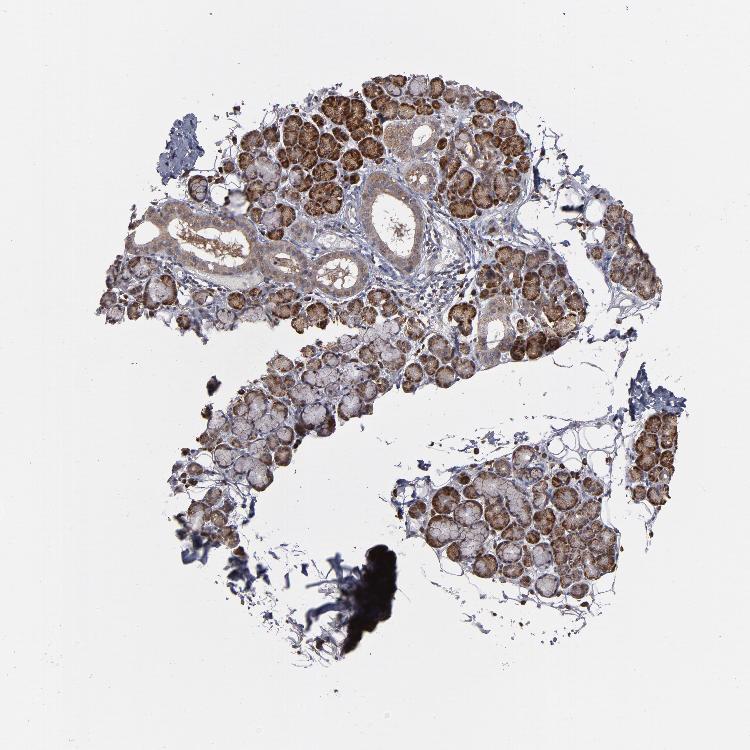

SALIVARY GLAND - Antibody stainingi

Antibody staining in the annotated cell types in the current human tissue is reported as not detected, low, medium, or high, based on conventional immunohistochemistry profiling in selected tissues. This score is based on the combination of the staining intensity and fraction of stained cells.

Each image is clickable and will lead to virtual microscopy that enables deeper exploration of all samples and also displays staining intensity scores, fraction scores and subcellular localization as well as patient and tissue information for each sample.

Antibody HPA002529Antibody HPA002632Antibody CAB019323

Glandular cells HighHighHigh